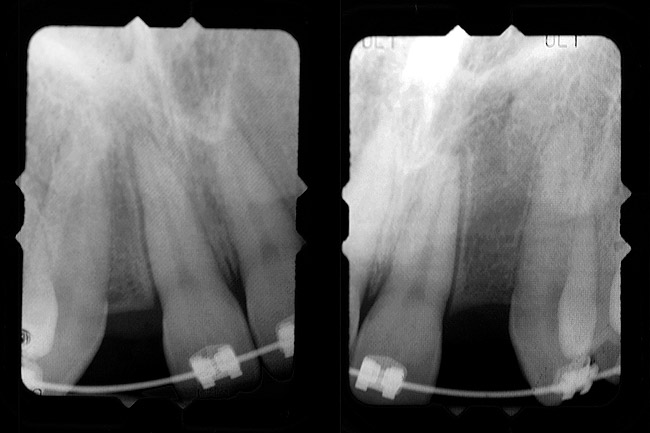

Periapical radiographs were taken to help determine the mesial-distal inclinations of the adjacent tooth roots (Figure 1). The radiographs revealed a serious issue, convergent roots for the right canine and right central, which eliminated that area as a potential implant-receptor site. The space between the left central and canine teeth was minimal, although the roots were relatively parallel. Clinical examination (manual palpation of the root eminences superiorly to the vestibule on the right side) confirmed the root convergence (Figure 2A). The flat, wide zone of the keratinized tissue and lack of interdental papilla was evident for the missing right lateral incisor. There was a marked difference in clinical appearance for the left lateral, which could impact the eventual plan of treatment (Figure 2B). Other significant clinical findings included bilateral facial bone concavities, which existed as a result of the congenitally missing tooth roots. As a diagnostic cue to the underlying bone topography, it is important to follow the demarcation between attached and unattached gingival tissue, and note the crestal width of the available keratinized tissue (Figure 2C).

Figure 1  Pretreatment radiographs revealed convergent roots for the right canine and right central.

Figure 1